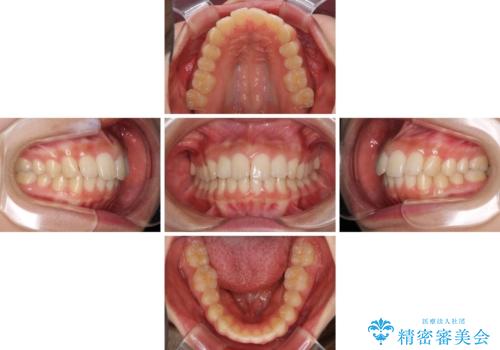

就職前にきれいな歯並びにしたい 大学生のインビザライン矯正

- 就職するまでに歯並びをきれいにしたいとのことで来院された患者様です。

前歯の叢生を気にしていましたが、極力突出感を改善できるようにすることとし、インビザラインにて矯正治療を行うこととしました。

改善の期待できない口元の突出感改善を希望されたため、いたずらに治療期間が延びましたが、きっちりと仕上がりました。